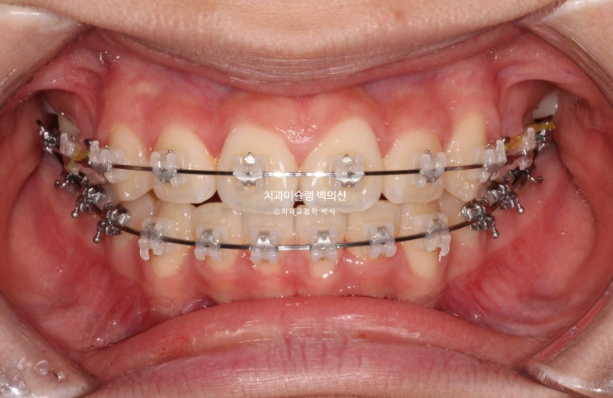

치료시작 1년째 모습입니다.

24.02

상악 발치공간은 편측으로 약 1/3 남아있으며 아직 한쪽 제2대구치가 나오지 않은 상황입니다.

두번째 큰어금니가 나오길 기다리며 치료를 천천히 이어갑니다.